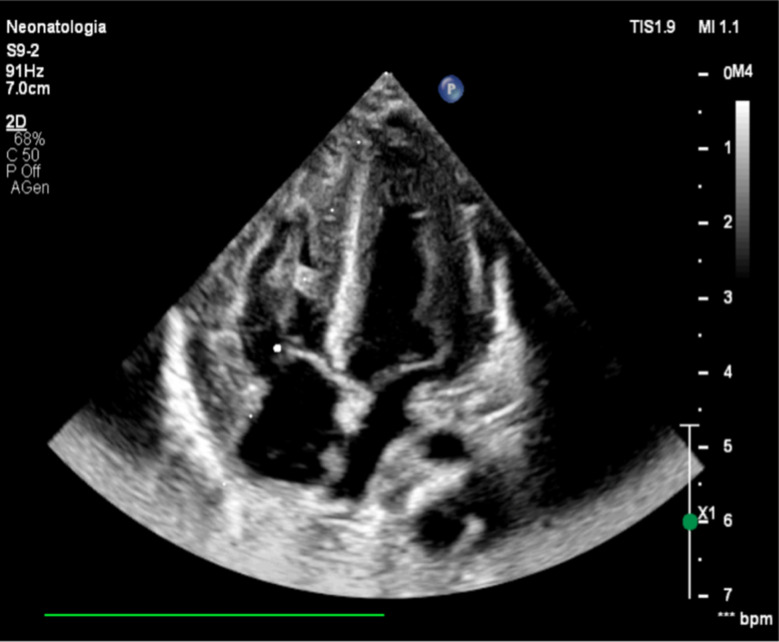

Case presentation: We present a case report of a male infant, inborn and delivered at a gestational age of 39 weeks. Medical history reveals consanguineous parents with no invasive screening tests performed during pregnancy. They chose not to undergo prenatal screening even though they were aware of the risks associated with their consanguinity. At birth, the newborn was atonic and pale, with a heart rate of 70 bpm. During resuscitation, an umbilical venous catheter was placed, and three doses of adrenaline and one dose of bicarbonate were administered. At the Neonatal Intensive Care Unit, he underwent therapeutic hypothermia. Echocardiography, performed a few hours later, revealed severe biventricular and septal hypertrophy consistent with non-obstructive hypertrophic cardiomyopathy. During recovery, even after the discontinuation of hypothermia, the newborn exhibited abnormal neurological signs, including axial hypotonia and a tendency to keep his mouth open with tongue protrusion. Given the clinical picture and the early detection of septal and biventricular hypertrophy, genetic testing was performed, revealing a homozygous c.2560 C > T variant in the acid alpha-glucosidase gene (both parents were carriers), described in scientific literature as a class 5 pathogenic variant associated with glycogenosis type II (Pompe disease).